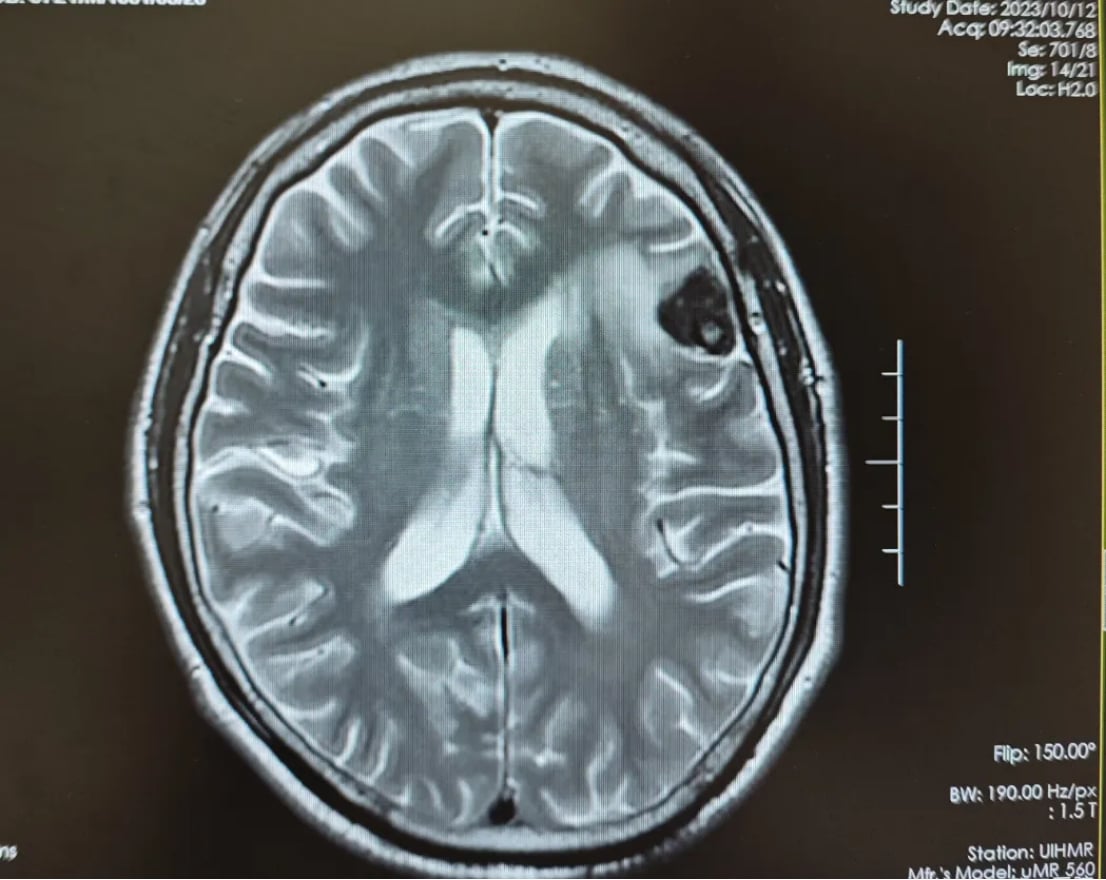

- 治疗4周期后:再次复查,病灶及水肿进一步缩小,病情得到有效控制,疗效评价为部分缓解(PR)。

图3 化疗4周期后复查影像